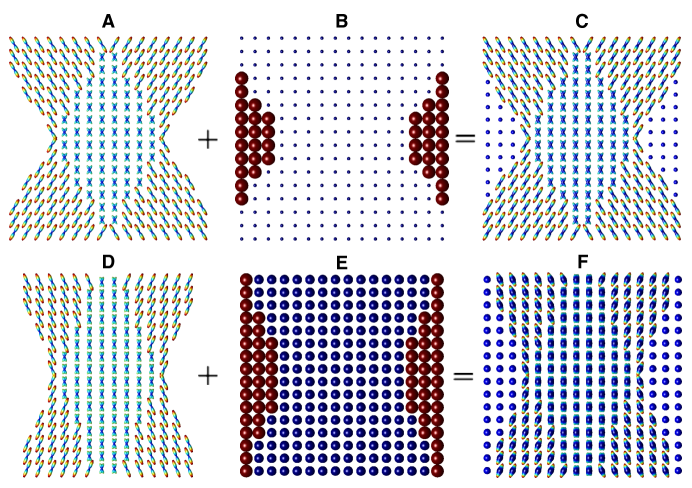

The performance of the proposed and reference methods has been assessed using both computer-simulated and real-life data. Specifically, the simulated data were generated based on a standard Gaussian mixture model [23] with FA=0.8 and MD = mm2/s (which corresponds to mm2/s and mm2/s). The spatial dimensions of the data were set to be equal to , while the directions of diffusion encoding were defined by the 2nd order tessellation of icosahedron restricted to the northern hemisphere of (thus resulting in sampling points). The data were designed so as to emulate a crossing of two cylindrically symmetric “fibres” of 8 voxels in diameter, with the crossing angle in the range with step size . Subplots A and D of Fig. 2 depict the theoretical ODFs corresponding to the middle “layer” of two signal arrays which have been synthesized for and , respectively. Additionally, to allow investigation of the effect of isotropic diffusion on the accuracy of SD-based reconstruction, the simulated signals have also been combined with a constant (i.e., isotropic) component of a variable magnitude. The diffusivity of the isotropic component was set to be equal to mm2/s, whereas its partial volume fractions outside and inside of the “fibres” were set to 1 and , respectively, with . Two examples of the isotropic component are shown in Subplots B and E of Fig. 2 for the case of and , correspondingly. (Note that, in the above subplots, the absolute size of the glyphs has been optimized for visualization, and thus it does not represent the actual values of the isotropic ODFs.) Finally, Subplot C of Fig. 2 depicts combined ODFs obtained as a result of the summation of the ODFs shown in Subplots A and B, while the result of the summation of the ODFs in Subplots D and E is displayed in Subplot F of the same figure.